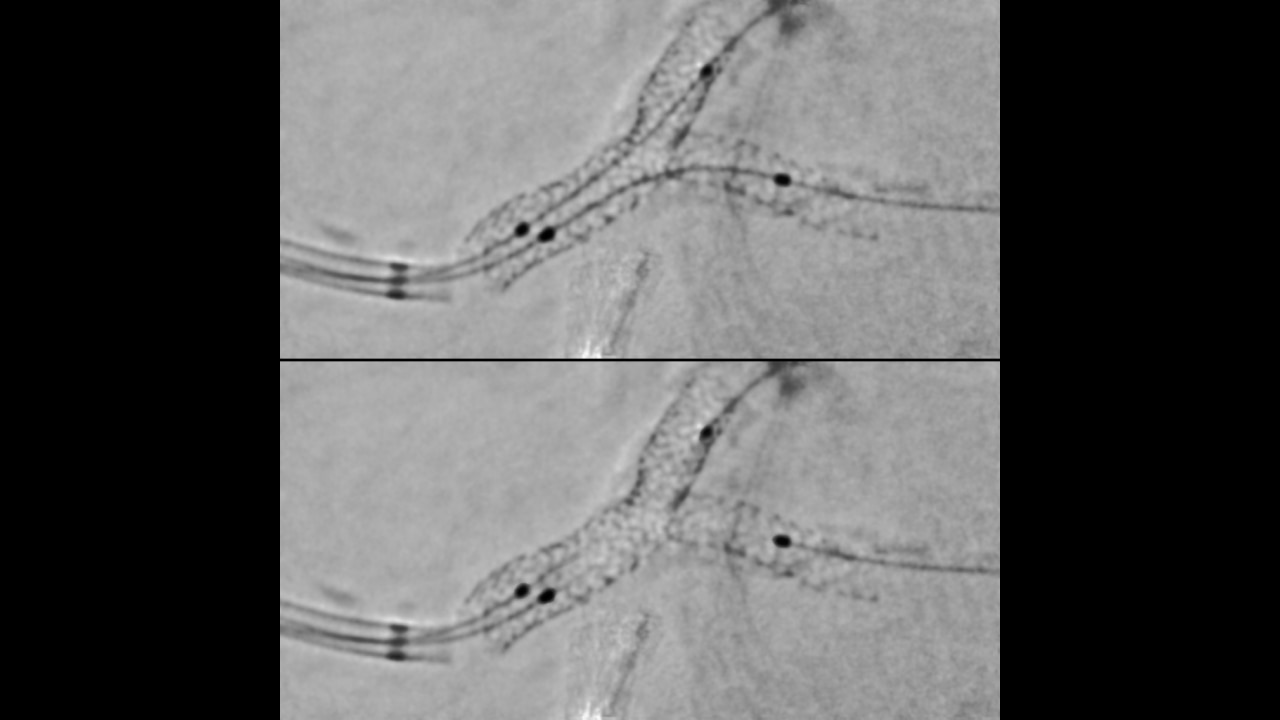

Guide

Augmented 2D image guidance

Help to increase positioning accuracy and confidence in multiple stent positioning.

Enhance the visibility of both stents in a bifurcation thanks to our improved StentViz algorithm.

Save time thanks to an automatic single acquisition workflow.

Improve anatomical visibility by up to 85%3,4 in moving arteries at the same radiation dose.